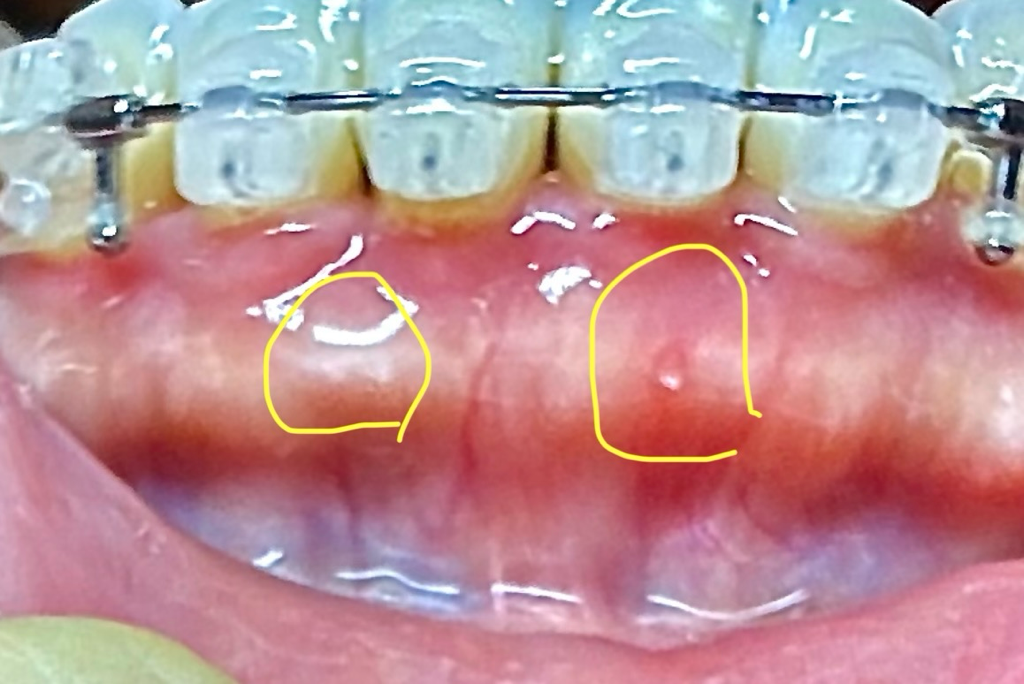

저 부분은 교정을 해서 튀어 나온게 아니라 잇몸뼈가 원래 저렇게 생겻을꺼에요. 교정을 한다고 잇몸뼈가 갑자기 튀어 나오는 경우는 없습니다.

교정을 하다 보면 치아가 이동을 하면서 해당 부위의 뼈가 앞으로 나오는 경우도 있습니다. 크게 문제가 되진 않으나 걱정이 되신다면 치과에서 진료를 받아보는 것을 권유드립니다